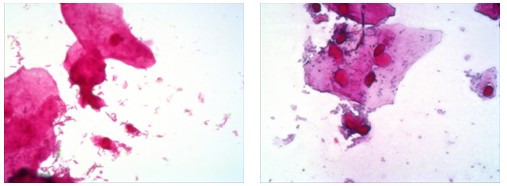

安圖公司目前主要是為終端用戶搭配一套用于分析記錄革蘭氏染色的數(shù)碼生物顯微鏡,廣州明美為鄭州安圖生物公司提供了高性價(jià)比的500萬像素顯微鏡相機(jī)MD50,并由武漢辦事處的工程師就近提供安裝培訓(xùn)服務(wù)。以下是廣州明美500萬像素顯微鏡相機(jī)MD50搭配奧林巴斯生物顯微鏡CX31所獲取的革蘭氏染色片子的高品質(zhì)顯微圖像:

革蘭氏染色分析

通過熒光顯微鏡|顯微鏡攝像頭|顯微鏡接口獲取的優(yōu)質(zhì)的革蘭氏染色的顯微圖像效果,用戶可以通過電腦屏幕輕松的進(jìn)行細(xì)菌的分析判斷,將雙眼從高強(qiáng)度的鏡檢中解放出來,大大降低勞動強(qiáng)度,同時(shí)可以方便的進(jìn)行信息的儲存以及共享。